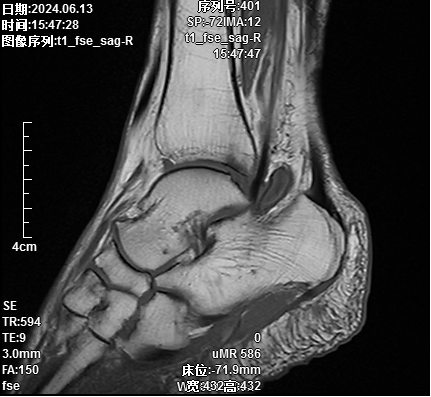

术前标记体位

术中精细操作,切除病灶